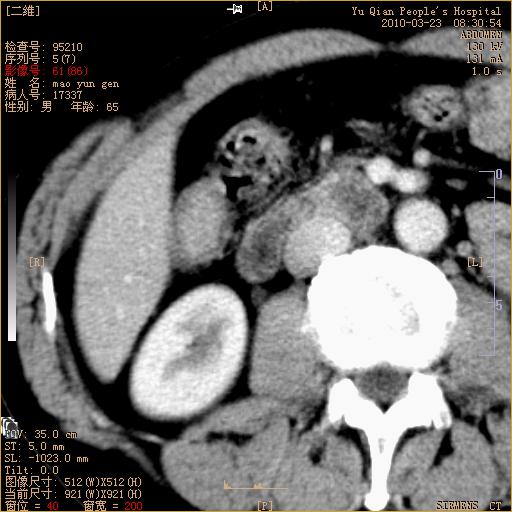

标题: CT25266:消瘦月余,前来肝部检查,请看看肠腔 [打印本页]

标题: CT25266:消瘦月余,前来肝部检查,请看看肠腔

肝区结肠占位,腺癌可考虑,建议肠镜活检。

升结肠肠壁增厚,不均强化,考虑升结肠腺癌可能性,建议肠镜检查。

1)考虑升结肠癌。2)右肾小囊肿。